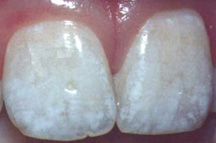

Ампициллин может провоцировать флюорозВ октябрьском номере журнала of Pediatric & Adolescent Medicine сообщается, что амоксициллин может привести к поражениям эмали зубов (флюорозу) у детей. Флюороз - один из самых частых дефектов развития зубной эмали, который связан с воздействием избыточного количества фторидов. При флюорозе отмечаются структурные изменения и деминерализация зубной эмали. Проявления флюроза варьируют от небольших пятен до безобразных сливающихся рытвин и отвратительных изменений цвета зубов. Ученые наблюдали детей в возрасте от 0 до 32 месяцев жизни. Употребление амоксициллина каждые 3-4 месяца увеличивал относительный риск поражения резцов верхней челюсти флюрозом более чем в два раза. По мнению доктора стоматологии из университета Огайо С. Пол, необходимы дальнейшие исследования данного феномена на экспериментальной модели . Проведение исследования поддержал Национальный институт здоровья США.